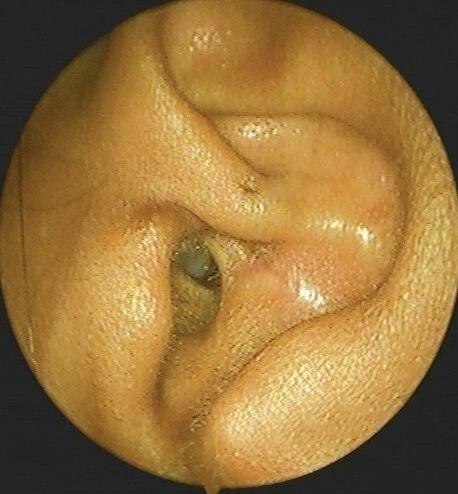

Fig. 1.1 Orelha normal. Esta é uma orelha direita de aparência normal. Os pontos de referência são (1) hélice, (2) anti-hélice, (3) fossa triangular, (4) fossa escafóidea, (5) trágus, (6) antitrágus, (7) concha da orelha, (8) lóbulo e (9) meato acústico externo.